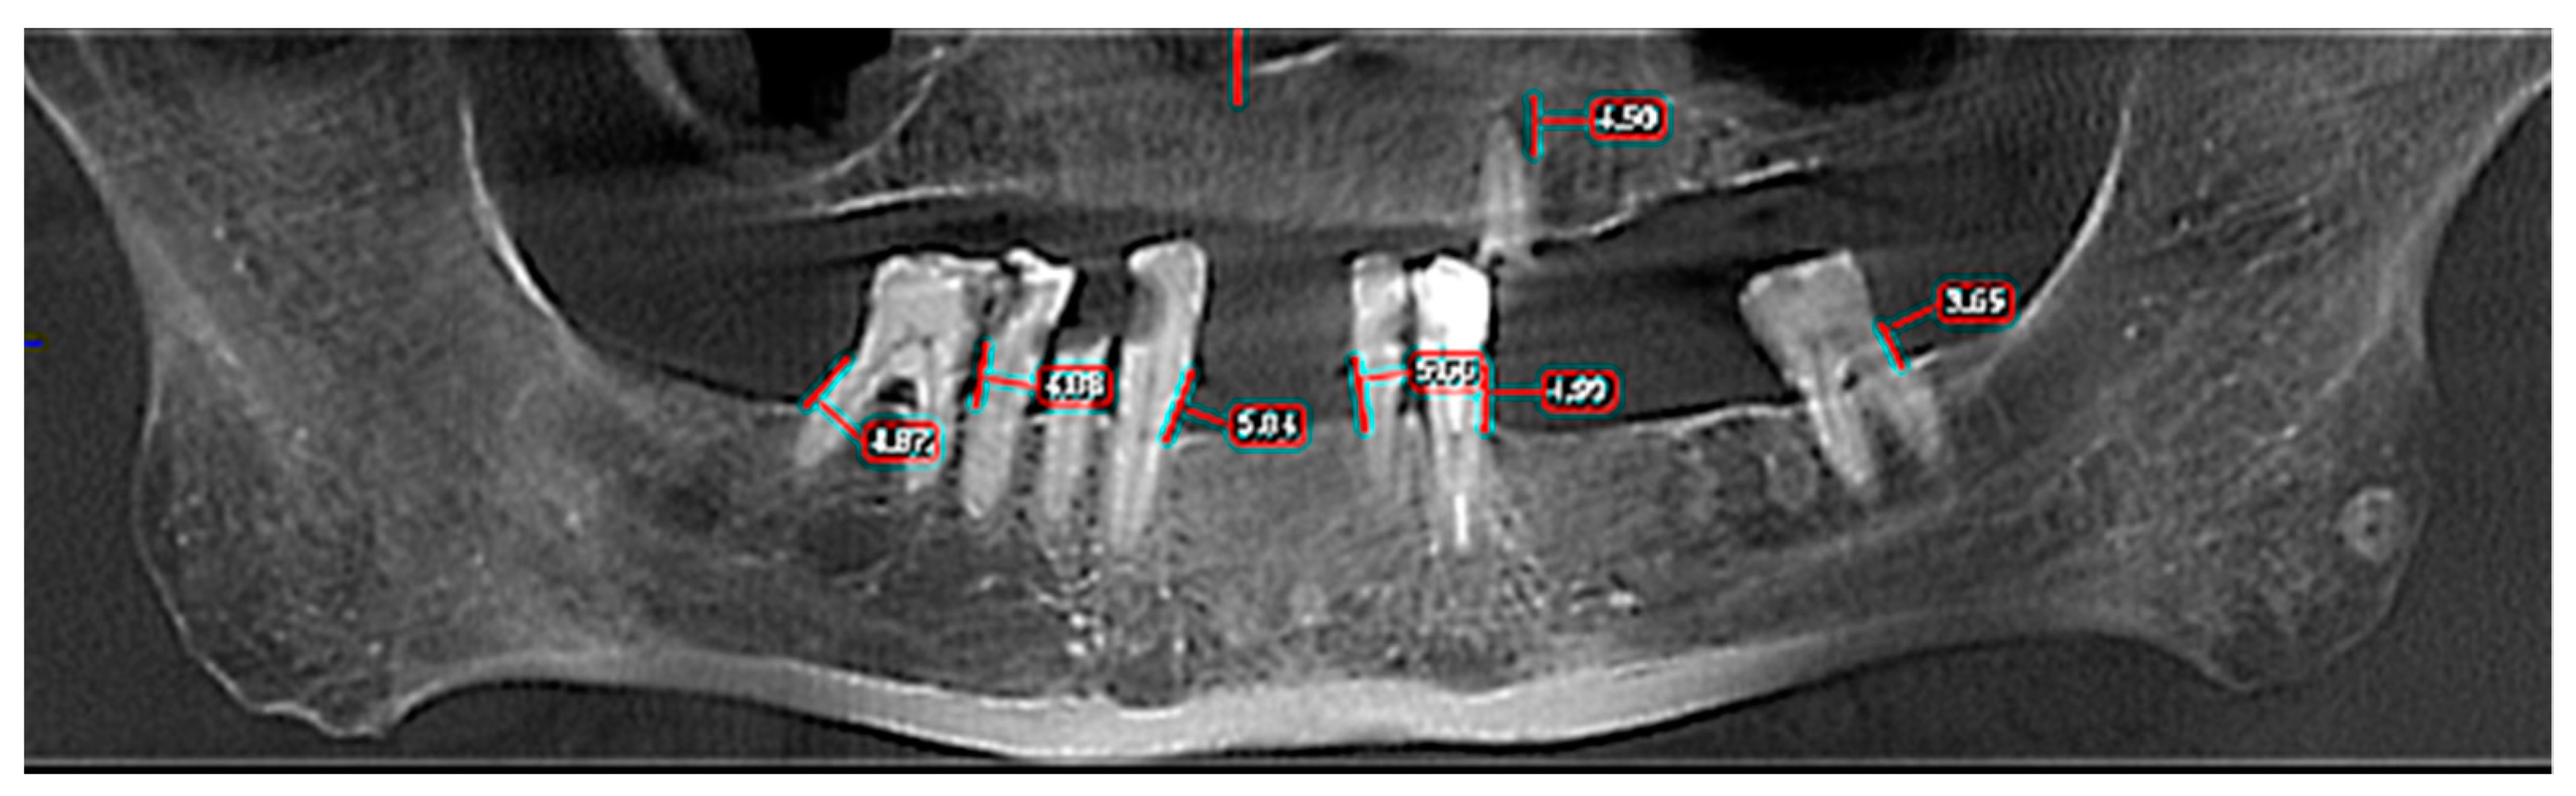

| Horizontal Bone Loss—Max Size | Group | Number | Mean | Standard Average Error | SD | Min | Max | Median | Student’s t Test |

|---|---|---|---|---|---|---|---|---|---|

| OPT | Control | 30 | 4.930 | 0.594 | 3.258 | 0.0 | 13.2 | 4.60 | t = −0.373 |

| ENT Cancer | 33 | 5.191 | 0.367 | 2.109 | 0.0 | 11.3 | 5.00 | p = 0.711 | |

| Total | 63 | 5.067 | 0.340 | 2.698 | 0.0 | 13.2 | 4.80 | ||

| CBCT 3D | Control | 30 | 5.736 | 0.633 | 3.471 | 0.0 | 14.10 | 5.75 | t = −0.548 |

| ENT Cancer | 33 | 6.152 | 0.438 | 2.519 | 0.0 | 12.40 | 6.17 | p = 0.586 | |

| Total | 63 | 5.954 | 0.377 | 2.992 | 0.0 | 14.10 | 6.00 |